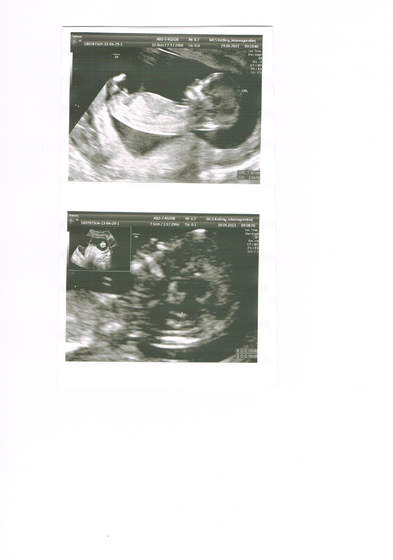

Trochę poczekaliśmy bo mój lekarz robił cc, wziął mnie na usg genetyczne (mąż był ze mną) no i wszystko jest super, dzidziuś zdrowy

Z usg wychodzi 13 tydzień 4 dzień. Kolejne usg gdzieś w 20 tygodniu...

A to nasz.. chłopczyk. Nie potrafię inaczej tych fotek ze skanera wrzucić.